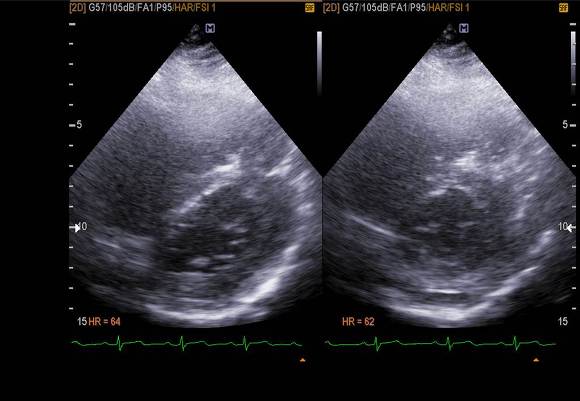

pic 3. PSX - systole 시 septum이 flattening 해짐.

pulmonary hypertension 으로 인해 D-shape  보였습니다.